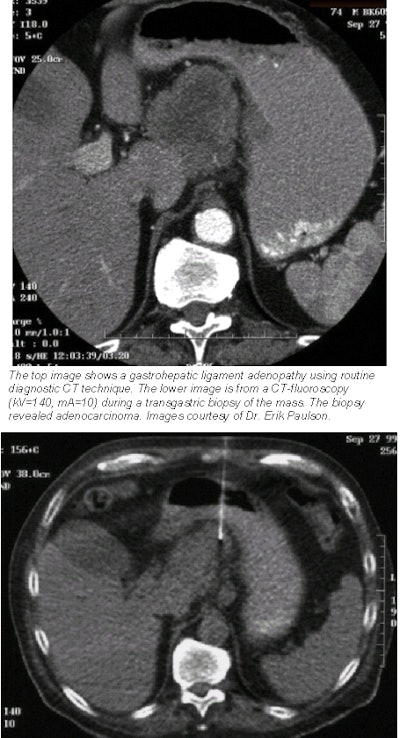

![]() |

The team also measured scattered radiation dose by using a standard anthropomorphic phantom and their most frequently used technical parameters of exposure (140 kV, 10 mA). At a distance of 25 cm from the section, the dose rate was 23 mrem per hour. When measured at 60 cm from the section, the scattered dose rate was 12 mrem per hour.